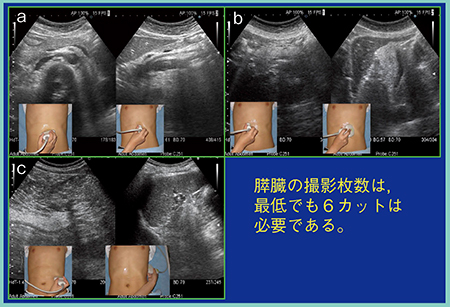

膵癌の超音波によるスクリーニングで十分な診断を行うためには,最低でも6カットの画像数は必要と考える。

まず,膵臓全体の長軸像と,上腸間膜動脈が見えてくる部分から膵体部までの2カットを1枚目とする(図1 a)。次に,プローブを縦にして走査し,膵頭部と,膵体部から膵尾部の脾臓に至る部分までの2カットを2枚目とする(図1 b)。膵癌は約7割が膵頭部に発生するため,非常に多くの情報を含む膵頭部の縦の走査による画像は,スクリーニングに必須である。最後に,左の季肋部から左の側腹部に向けた横走査を行うことで,脾静脈の上に膵臓が描出される(図1 c)。この走査は一般的にあまり行われていないが,必ず追加すべき1枚である。通常行っている左肋間走査では膵臓は不明瞭なことがあるが,それは膵臓への脂肪浸潤のため脂肪肝と同様に超音波が減衰することも原因である。そのため,直角に超音波ビームが当たるこの横走査は非常に重要であり,膵管が直交して描出されるメリットもあり必要なカットである。

図1 膵臓のスクリーニングに必要な超音波画像